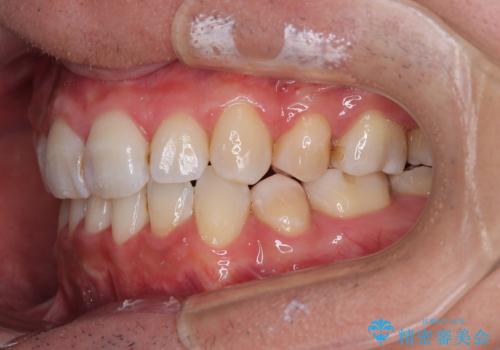

顎が左右にずれた咬み合わせ ハーフリンガルの抜歯矯正

それでも想定以上に治療期間は長期化せず、咬み合わせも口元も満足のいく仕上がりとなりました。